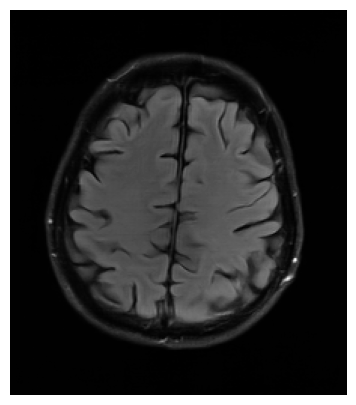

We used the PSNR and SSIM metrics to quantitatively compare the reconstructed magnitude image and the ground truth. They are given for each contrast and for the 2 acceleration factors in the Figs. 2- 3. Similar results are available on the public fastMRI leaderboard333fastmri.org/leaderboards, although generally slightly better. It is a bit difficult to consider these results when compared to only the zero-filled metrics, but these quantitative metrics do not accurately capture the performance of the GRAPPA algorithm [2]. However, at the time of submission, this approach ranks 2nd in the fastMRI leaderboards for the PSNR metric, and finished 2nd in the 4 and 8 tracks of the fastMRI 2020 brain reconstruction challenge [16].

Qualitative.

The visual inspection of the images reconstructed (available in Fig. 2) at acceleration factor 4 shows little to no visible difference with the ground truth original image. However, when increasing the acceleration factor to 8, we can see that smoothing starts to appear which leads to a loss of structure as can be seen in Fig. 3.

| T1 PSNR: 41.56 SSIM: 0.9506 | T2 PSNR: 40.68 SSIM: 0.9554 | FLAIR PSNR: 39.60 SSIM: 0.9321 | T1POST PSNR: 42.53 SSIM: 0.9683 |